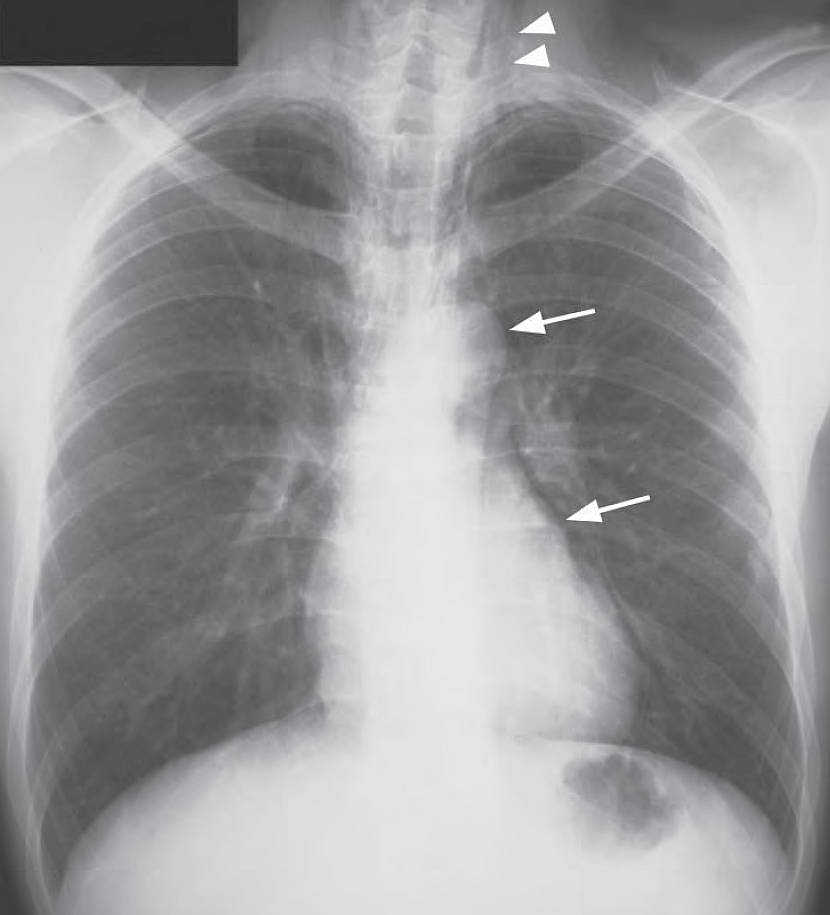

Chest X-Ray Interpretation

- Air lucency in mediastinum outlining the left heart border and aortic knuckle (arrows).

- Subcutaneous emphysema in the lower neck (arrowheads).